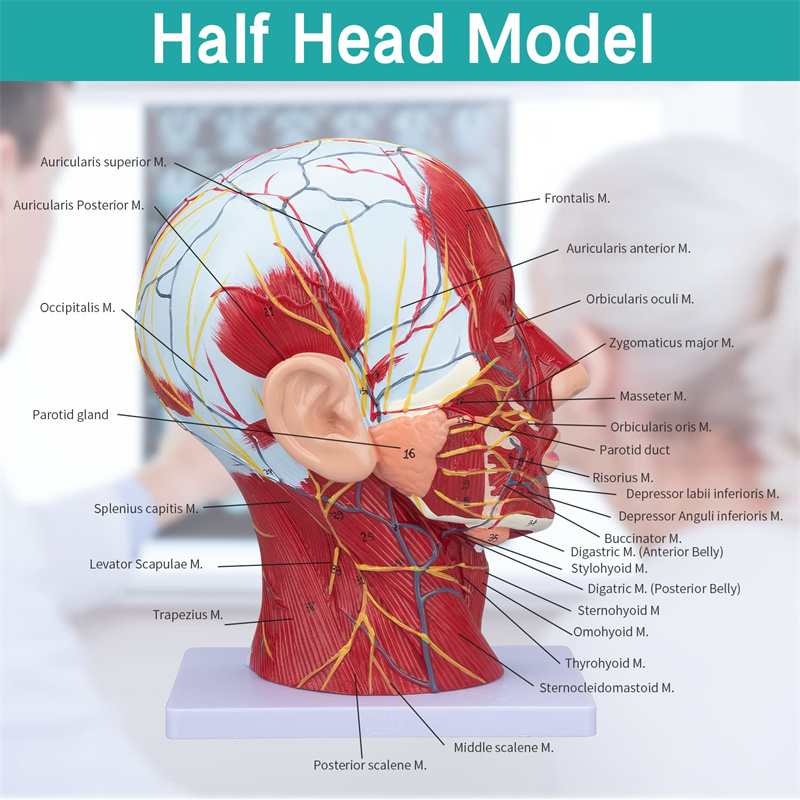

【Ciri -ciri】 Ia menunjukkan otot -otot cetek muka yang terdedah; saluran darah cetek & saraf muka & kulit kepala; struktur dalaman kelenjar parotid & saluran pernafasan atas; Struktur keratan rentas sagittal tulang belakang serviks.

Model ini menunjukkan butiran leher kepala kanan dan bahagian pertengahan sagittal manusia. termasuk cetek

otot muka yang terdedah; saluran darah dangkal dan saraf muka dan kulit kepala; struktur dalaman

kelenjar parotid dan saluran pernafasan atas; Struktur keratan rentas sagittal tulang belakang serviks.

Model ini adalah model otot neurovaskular yang besar dan leher yang besar, 1 komponen, menunjukkan butiran kepala kanan dan leher manusia dan bahagian sagittal median, termasuk otot -otot dangkal yang terdedah pada muka, kapal cetek muka dan skalp, saraf, saraf, saraf, saraf, saraf, saraf, saraf, saraf, saraf, saraf, saraf, saraf, saraf, saraf, saraf, saraf, saraf, saraf, saraf, saraf, saraf, saraf, saraf, saraf, saraf, saraf, saraf, saraf, saraf, saraf, saraf, saraf, saraf, saraf, saraf, dan struktur medial kelenjar parotid dan saluran pernafasan atas, dan struktur bahagian sagittal tulang belakang serviks